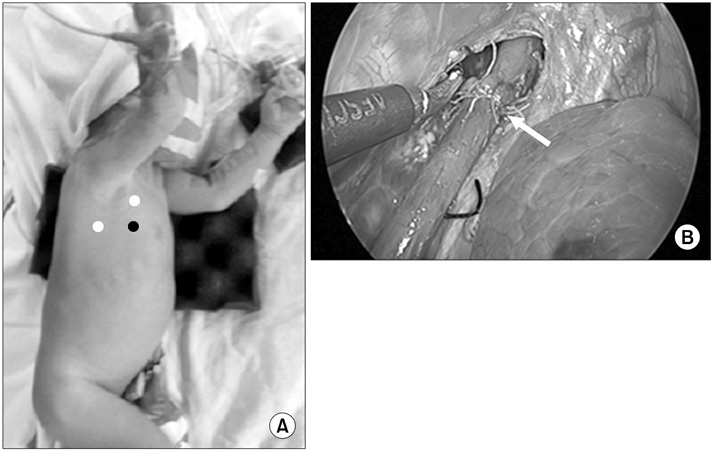

Fig. 1

Esophageal atresia (EA) with tracheoesophageal fistula. (A) Position of patient for operation of EA (white dots, working port; black dot, camera port). (B) After ligating azygos vein, fistula was also ligated with simple suture, and end-to-end anastomosis of esophagus was done with interrupted suture. Arrow, end-to-end anastomosis site.

Fig. 1 Esophageal atresia (EA) with tracheoesophageal fistula. (A) Position of patient for operation of EA (white dots, working port; black dot, camera port). (B) After ligating azygos vein, fistula was also ligated with simple suture, and end-to-end anastomosis of esophagus was done with interrupted suture. Arrow, end-to-end anastomosis site.